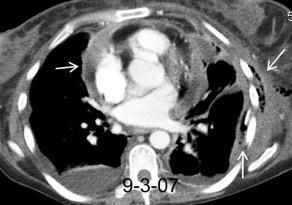

Masa axilar izquierda y derrame pleural derecho. Implantes pleurales, paraespinales . Ganglios en mamaria interna. Linfoma B difuso

Linfoma NH de cél. B. Invasión Transtorácica.

Afectación axilar